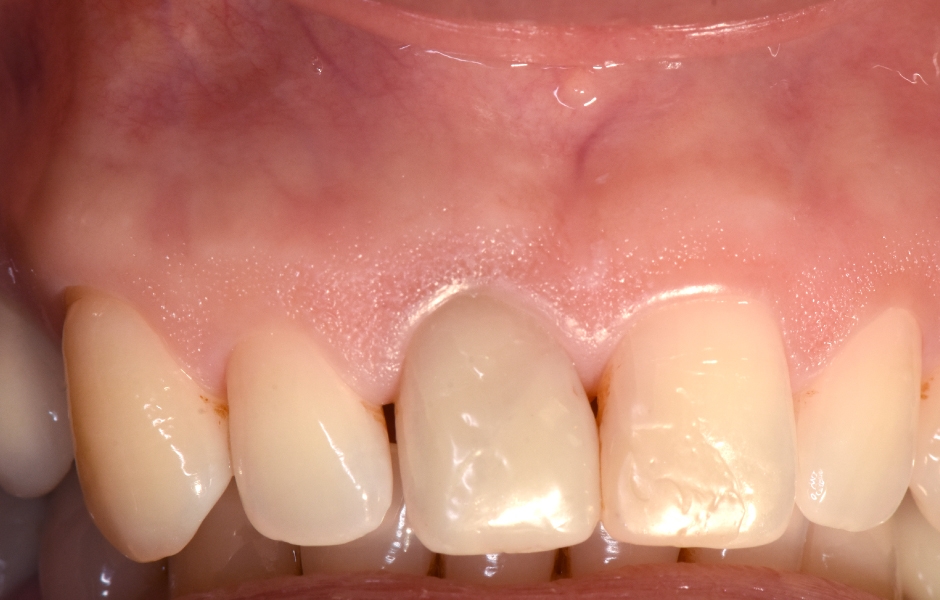

Obr. 1.5: Odstranění sutur po 48 hodinách a kontrola po třech letech – kompletní absence jizvy.

Obr. 1.6: Kontrola po třech letech.